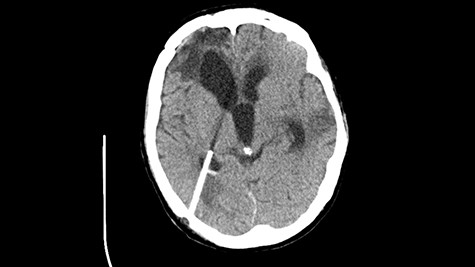

Head CT—state before VP shunt implantation. (Department of Neurosurgery own material).

The patient was qualified for VP shunt implantation, during which elevated cerebrospinal fluid pressure, above 300-mm H2O, was found. Further small improvement in neurological status was obtained. Periodically we observed increased body temperature and increase in laboratory exponents of inflammation (after an earlier decrease to values close to normal). There were several convulsive epileptic seizures with loss of consciousness with no response to benzodiazepines, therefore thiopental was administrated, patient was intubated and ventilation therapy started. In the course of further hospitalization the body temperature increased to over 39°C, with an increase in inflammatory markers. Positive blood cultures (Staphylococcus epidermidis), urine (Klebsiella pneumoniae and Pseudomonas aeruginosa) and bronchoalveolar lavage (P. aeruginosa) were obtained. Empirical treatment was applied followed by targeted antibiotic therapy. There was a gradual improvement in the general and neurological status—up to GCS 14. Negative blood, urine and mini-bronchoalveolar lavage (mini-BAL) cultures were obtained. The tracheostomy tube was removed and the tracheostomy hole was closed. A few days later there were two epileptic seizures and further deterioration in the general and neurological condition, therefore the patient was re-intubated, mini-BAL was performed. The next day in the morning hours, seizures occurred several times, initially regressing after administration of Relanium, then not responding to this drug. Depakine administrated in the i.v pump. A day later, in the morning, there was a seizure again. Thiopental was administrated, ventilotherapy started. A lumbar puncture was performed showing a cerebrospinal fluid without inflammatory features. Finally, the patient condition improved slowly over time.

After improvement of patient’s neurological status, a CT scan of the head revealed enlargement of the ventricular system with the features of cerebrospinal fluid transudation (Fig. 2), thus the patient has been qualified for a VP shunt implantation (Fig. 6).